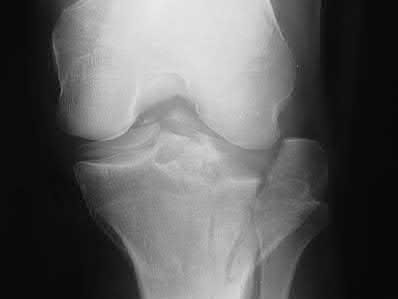

A 22-year-old male cyclist was struck by a car. He complains of right knee pain and swelling, as well as reduced sensation and weakness in his right foot. His leg compartments are soft and not tender. Distal pulses in the extremity are palpable. Radiographs of the knee, as shown in Figures A and B, were taken after a closed reduction maneuver was performed. What would be the next best step in management of this patient?

This patient presents with a Schatzker IV tibia plateau fracture with lower extremity neurologic deficits. The next best step would be to investigate for an acute vascular injury with ankle-brachial index measurements.

Fracture-dislocations of the knee must be suspected with all Schatzker type IV injuries as this fracture pattern is usually associated with high energy trauma. Identifying this injury should prompt a thorough assessment of the neurovascular structures across the knee. After closed reduction and emergent immobilization of the knee, ankle brachial indices (ABI) must be immediately performed. If